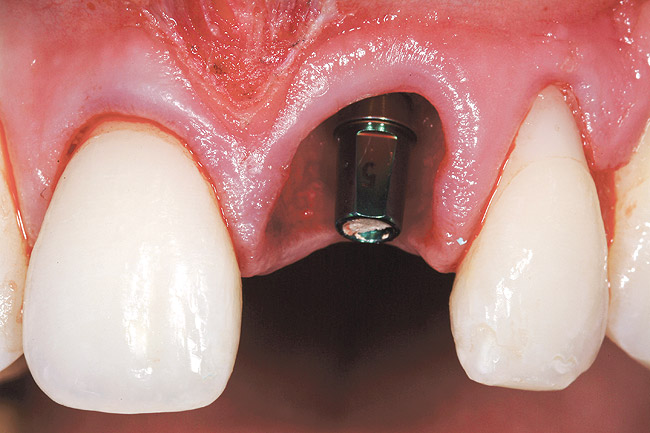

A 24-year-old non-smoking man presented for treatment of a horizontally fractured left central incisor (Figure 21 and Figure 22). The patient requested to have an implant placed to replace the left central incisor as to not have any damage to the adjacent dentition.

Complicating the treatment site was the apically positioned facial height of contour at the left central incisor, and the adjacent left lateral incisor (Figure 21.) Additional sites of recession were present throughout the oral cavity and were to be addressed by the tunnel grafting procedure previously outlined.

The patient opted for the third option. After administration of an appropriate local anesthetic, a frenectomy was performed using a Nd:Yag laser. This would allow for the loosening of the facial tissues and the coronal repositioning of the pouch at the termination of the procedure. After the frenectomy, the left central incisor was removed by an atraumatic technique preserving the soft tissue emergence profile (Figure 23). Debridement of the extraction socket preceded atraumatic site preparation techniques. A 3.5-mm diameter by 13-mm tapered implant (Prima Connect, Keystone Dental, www.keystonedental.com) was placed to the appropriate depth measurements planned.38,39

Once the implant was seated, the cover screw was placed, and the facial defect at the buccal aspect of the implant was corrected using mineralized, large-particle cancellous chips (Lifenet, www.lifenet.org) and a solution of PRP, forming a graft/PRP gel complex. The graft complex was heavily condensed into the void present, to the level of the facial aspect of the polished collar on the implant (Figure 24).

After placement of the graft complex, a titanium abutment with a 1-mm collar (Quick abutment, Keystone Dental) was seated and hand-tightened (Figure 25). Retrofitting of the natural tooth shell preserving the pre-existing contact point relationships and line-angle positioning was accomplished from a pretreatment incisal edge registration. The final provisional restoration can be seen in Figure 26.

Figure 21  Case Three Pretreatment view, Case Three, left central incisor.

Figure 21

Figure 23  Case Three Atraumatic extraction, left central incisor.

Figure 23

Figure 24  Case Three Minimally invasive bone grafting, occlusal view.

Figure 24

Figure 25  Case Three Titanium abutment seated

Figure 25

Figure 26  Case Three Immediate provisional restoration.